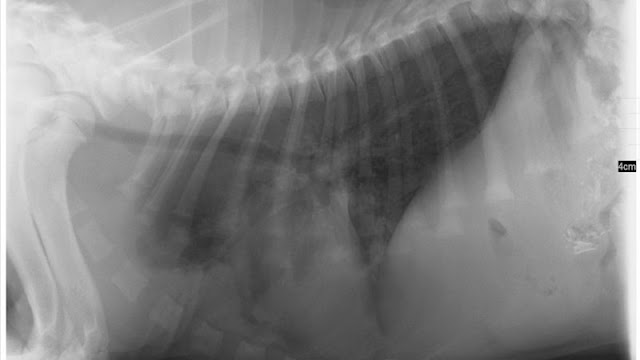

Esta infección por hongos puede derivar en una neumonía fúngica, a través de la inflamación de los pulmones. Esta infección se conoce como micótica.

La neumonía fúngica puede provocar lesiones en los pulmones y otros órganos afectados. Es habitual la formación de abscesos y lesiones cutáneas.